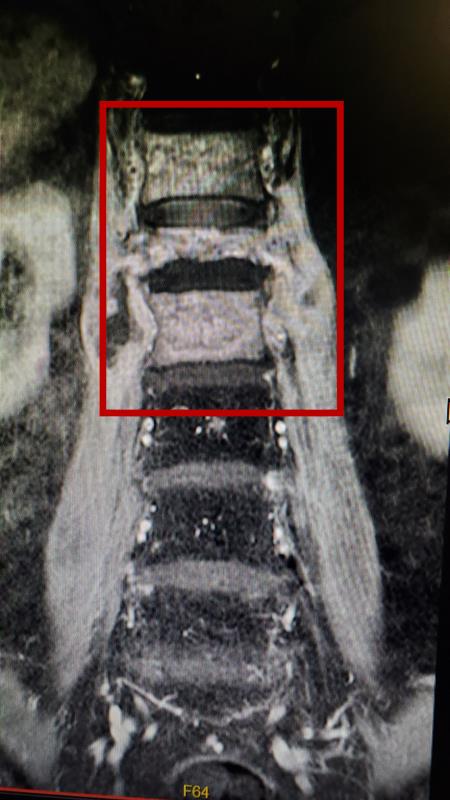

被结核杆菌侵蚀的三节脊椎骨

张老伯辗转来到广州医科大学附属第三医院骨科吴增晖主任处就诊,在体格检查中,吴增晖主任发现老伯下肢肌肉力量明显下降,可能已经出现了脊柱神经受损的情况。CT核磁共振检查结果如吴教授所料,张老伯第12胸椎、第1腰椎和第2腰椎椎体被严重侵蚀,第1腰椎就好像被"吃掉了";此外,椎体周围还形成了大量脓肿,对脊髓及神经造成压迫。